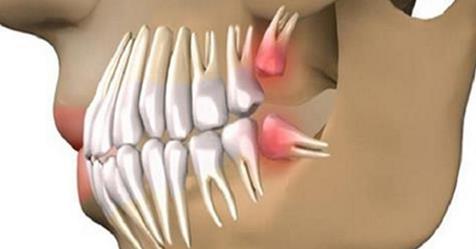

Новая технология позволит вырастить зуб во рту. Доктор Джереми Мао из Колумбийского университета создал зубы прямо из стволовых клеток и ДНК в организме.

Отсутствующий зуб заменяется стволовыми клетками, из Вашего собственного тела. И зуб сливается с окружающей тканью. Да, это просто! Это ускорит процесс регенерации, что приведет к быстрому восстановлению.